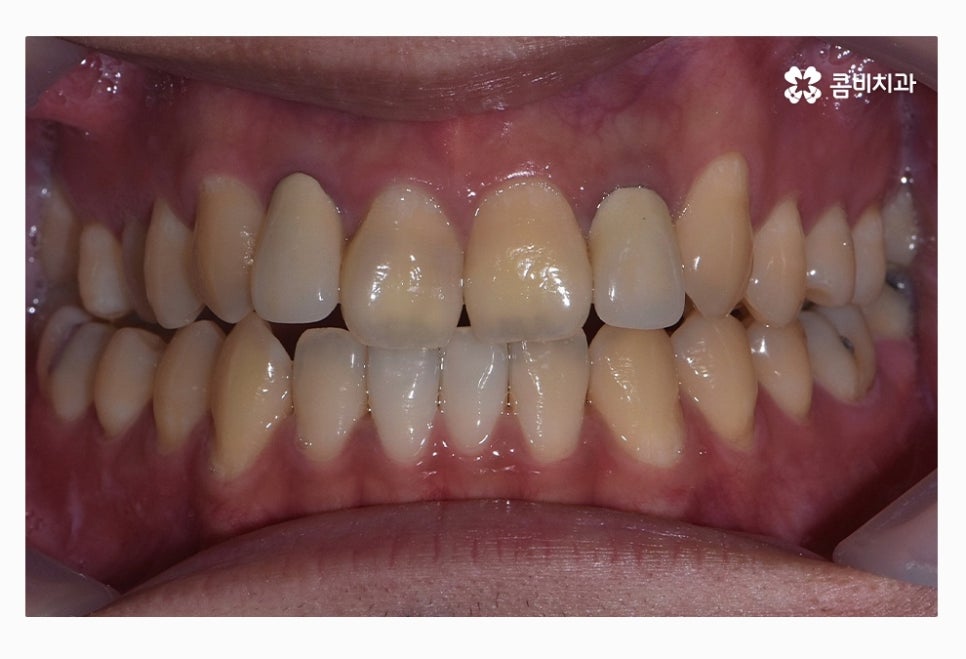

위 환자분의 경우 치열을 볼 때 정면에 비해서 측면으로 보면

앞니가 삐뚤어져 있는 것이 눈에 띄며 교합이 맞지 않아

윗니가 아랫니를 정상적으로 덮지 못하고 있는 상태이며

치아의 이동 공간 및 교합 등으로 볼 때 비발치로

치료가 가능했던 사례라고 할 수 있어요.